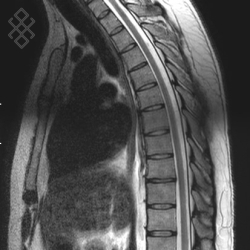

IRM Médullaire

Pour une IRM médullaire, aucune préparation n'est requise. Dans le cas d'une injection du produit de contraste, un cathéter vous sera posé par le personnel soignant. De même, en fonction de votre âge, le centre vous prescrira une prise de sang pour évaluer le taux de créatinine.

La durée moyenne de l'examen est de 25 min. Dans le cas d'une injection, le manipulateur en radiologie vous administrera le produit de contraste. Vous entendrez un bruit caractéristique à l'IRM faisant penser à un marteau piqueur.